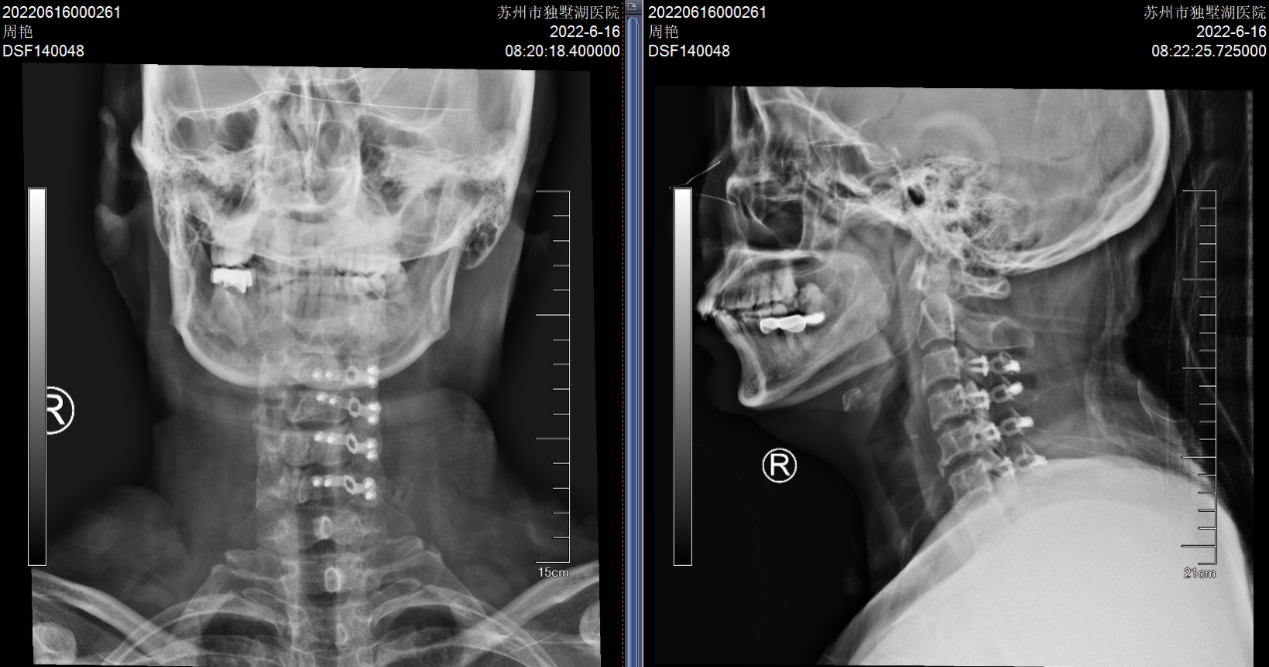

在沈阿姨术后第三天,其表姐王阿姨也在她的推荐下来住院了。王阿姨的症状和沈阿姨几乎一样,在住院的前1个月,她右上肢的疼痛感突然加剧,病变的节段是C5-6,看到表妹的手术效果如此显著,她决定也来做手术。

(C5-6 ACDF术,患者手术疗效确切)

(颈椎术后X片:C3-6椎管扩大成形术后)

(吕姐的接受的手术与吕弟一样,C3~6椎管扩大成形术。)